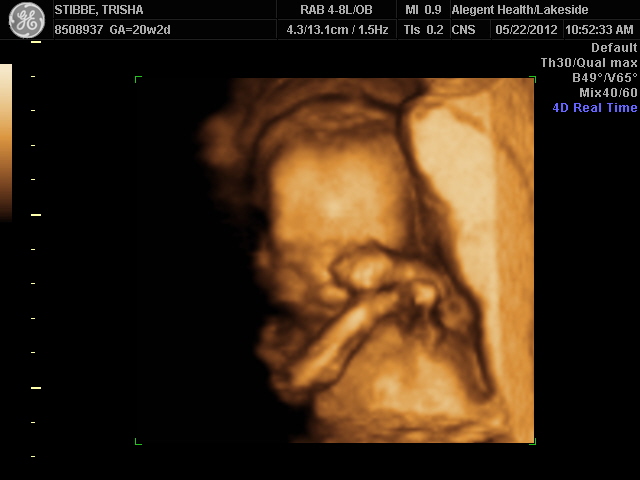

Ultrasound Day!